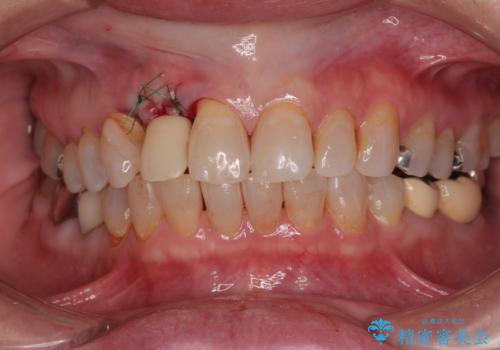

新幹線や飛行機を利用しても来院であり、極力来院回数を減らしたり、東京に用事があるタイミングに合わせてアポイントを調整したりと、負担が少なくなるようにして治療を進めて行きました。

来院間隔があいたため、予定よりも長くなりましたが、大きなトラブルもなく、外科処置は1回のみ、最小の来院数で無事に治療を終えることができました。